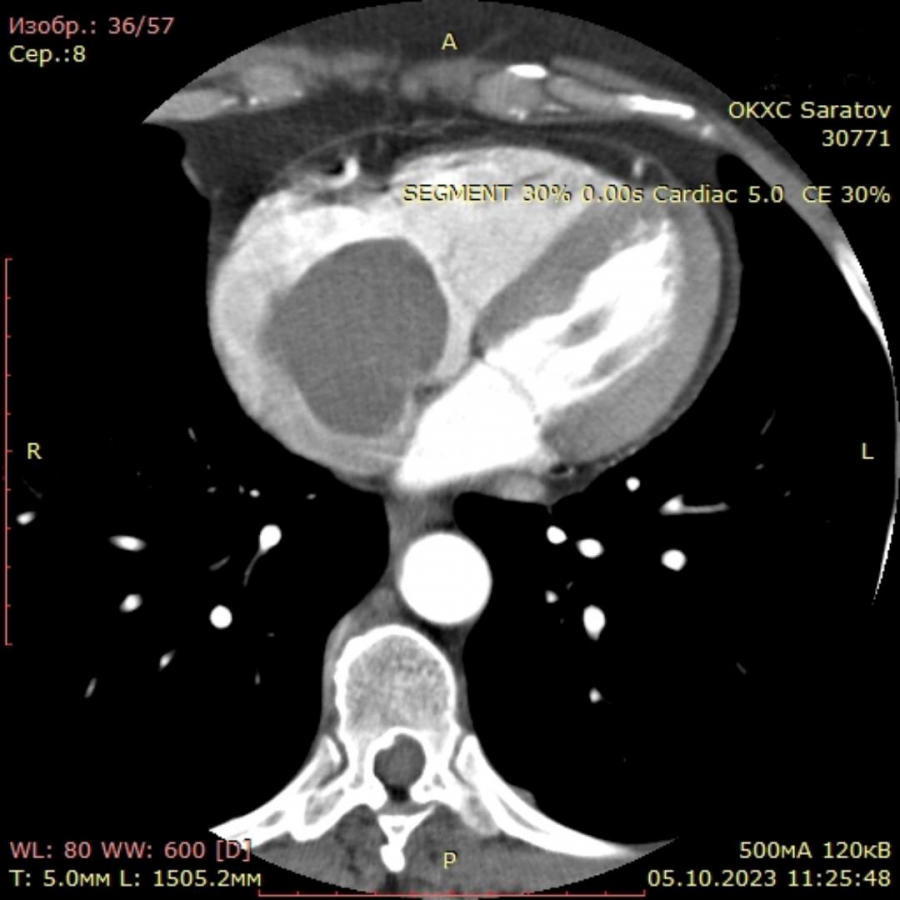

В кардиологическом диспансере женщине удалили крупную опухоль сердца

В Саратове хирурги прооперировали пациентку с крупной опухолью в сердце. Об уникальном случае из медицинской практики рассказали в областном клиническом кардиологическом диспансере.

В больницу 53-летняя женщина попала после жалоб на одышку при физической нагрузки. После детального обследования специалисты обнаружили в правом предсердии пациентки доброкачественную опухоль – миксому. По наблюдениям врачей, она оказалась довольно крупной - 6х4х4 см, при этом обнаружена именно в правом предсердии, когда в 86% случаев она появляется в левом. Опухоль вызвала у горожанки сужение правого атриовентрикулярного отверстия и гемодинамическое нарушение.

Заведующий кардиохирургическим отделением №2 Алексей Жуков рассказал, что болезнь коварна в длительности бессимптомного периода, когда размеры опухоли еще малы. Осложнением может стать разрастание образования до крупных размеров, его фрагментация, миграция фрагментов с током крови, что, в свою очередь, может приводить к эмболии (закупорке) крупных сосудов. В связи с этим врачи приняли решение о скорейшем оперировании пациентки.

«Оперативное вмешательство требует деликатной хирургической техники, чтобы во время удаления новообразования оно не фрагментировалось, не вызвало эмболии сосудов или рецидива. Кардиохирурги ОККД успешно удалили опухоль, пациентка в настоящее время выписана на амбулаторное лечение», - добавил Алексей Жуков.